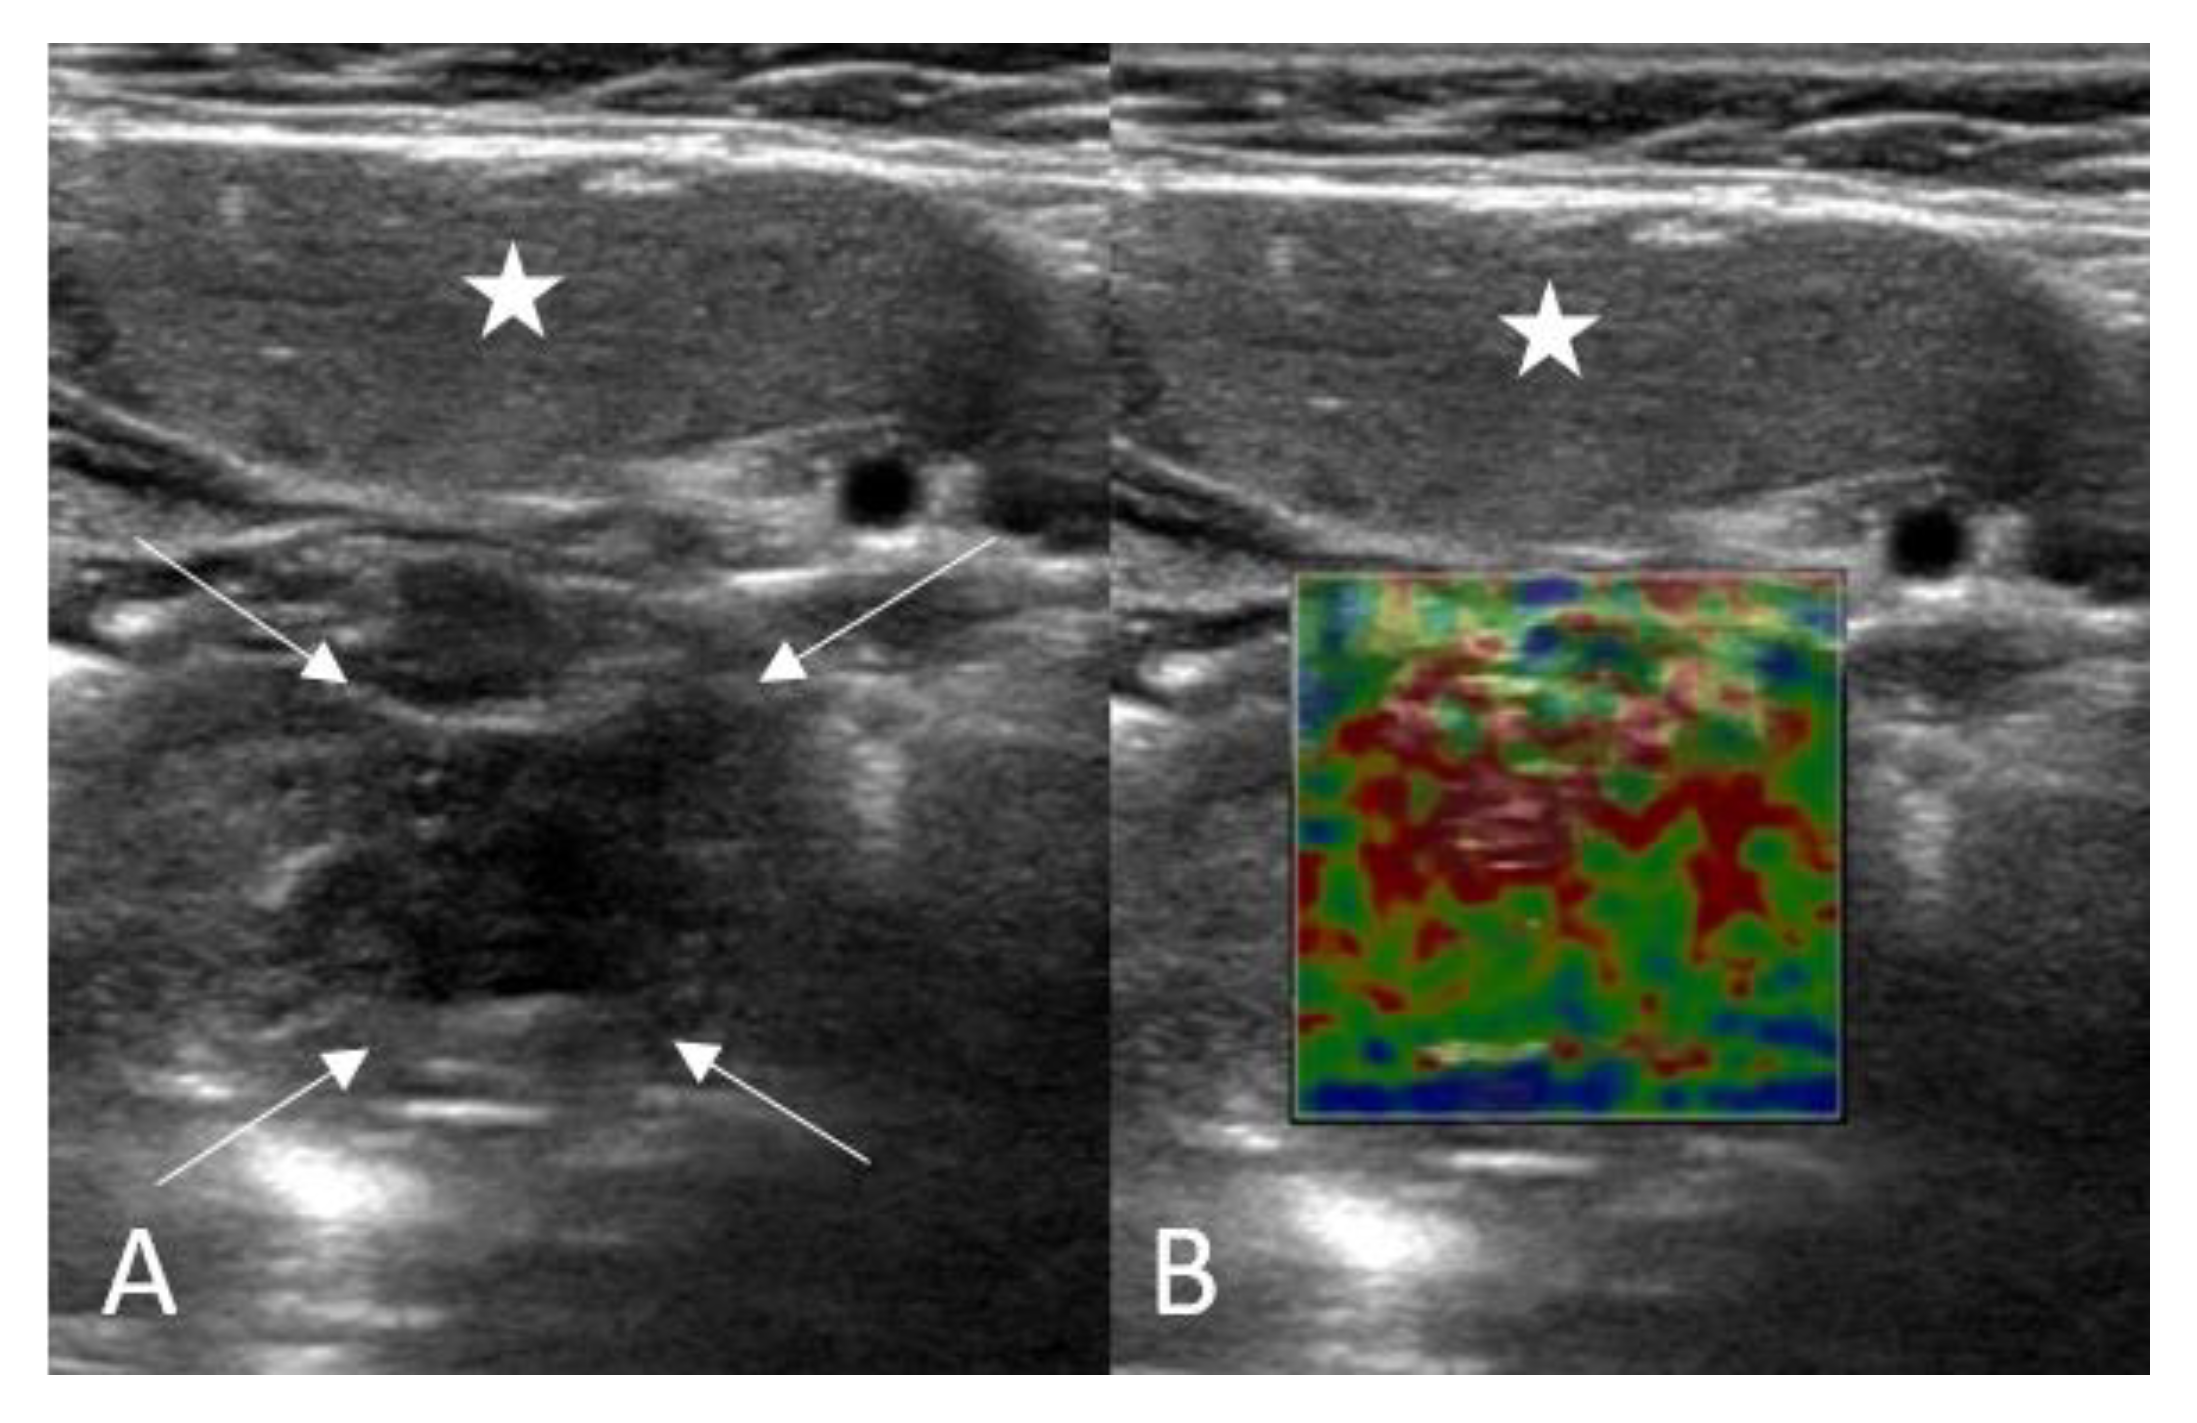

2.2. Ultrasound and Shear Wave Elastography Assessment